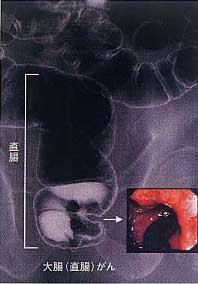

大腸がんは初期には無症状に進行します。何らかの自覚症状が現れたときには、ある程度病気が進行していることが多いようです。大腸がんの重要な症状として、下血や便に血が混じる血便があります。少量の出血の場合はほとんど目に見えません。そのため、顔色が悪いというような貧血の症状が出て初めて気づくことが多々あります。この目に見えない出血をとらえる方法として便潜血反応検査があります。無症状の早期の大腸がんをとらえる方法として最も簡単で有用な検査として、広く検診に用いられています。しかし、この検査にも弱点があります。早期大腸がんでは約30%、進行大腸がんでも約20%では陰性なのです。したがって、この検査ですべての無症状の大腸がんが発見されるわけではありません。確実に早期の大腸がんをみつけるには、やはり注腸透視や大腸内視鏡検査(図)を受けるしか方法がありません。50歳ぐらいからがんが発症しやすい年齢に差しかかります。できれば、症状がなくても一度大腸内視鏡検査を含む検査を受けてみられるか、少なくとも便に血が混じっていたり、貧血に気づいたり、便の潜血反応が陽性と判定されたらすぐに専門医を受診され、精密検査を受けられることをお勧めします。